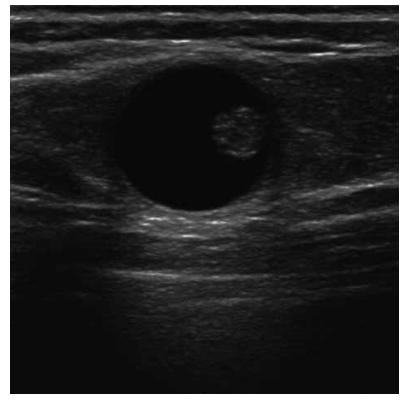

Uma paciente de 52 anos realiza ultrassonografia de mamas de rotina. O exame evidencia uma alteração focal na mama esquerda, conforme mostrado na figura a seguir:

Com base no caso e na imagem, qual a conduta mais adequada?